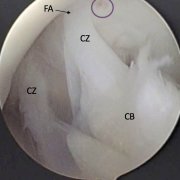

Figure 6B. Knee at 45° flexion. The IPP (CZ) is split in 2 bands, is attached to the apex of the femoral notch (FA) above, and spans the gap to the central body (CB) attachment to the fat pad. There is a zone of inflammation (circle) adjacent to FA. The central zone (CZ) is the ligament itself, the leading edge curved slightly suggesting laxity.